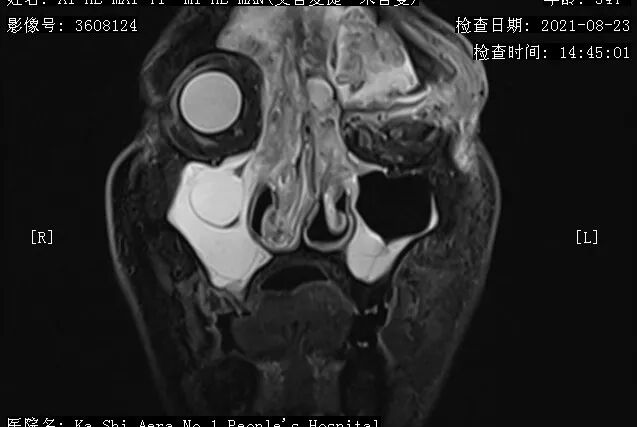

▲图丨术前患者症状和影像资料入院完善相关检查后,耳鼻咽喉科林勇副主任发现艾合买提的双侧鼻腔、上颌窦、额窦及左侧眼眶内弥漫性出现了软组织肿块,且左侧眼眶上壁、额窦前后壁局部骨质被破坏,左眼球突出严重,如不及时进行治疗,很可能危及生命。于是,他在第一时间联系科内专家进行讨论,并申请全院会诊。

“患者为复发型鼻腔鼻窦-前颅底内翻性乳头状瘤,‘鸡蛋’ 般大小肿瘤严重压迫患者的视觉神经,视力损伤严重,需尽快进行手术!”

术中,手术团队完全切除艾合买提的双侧鼻腔、鼻窦及左侧前颅底和眶内侧壁肿物,同时进行左侧眶减压重建+前颅底修复。术后复查鼻窦+眼眶强化MRI,其颅底肿物完全清除,不适感明显减轻,左眼视力较术前明显改善。